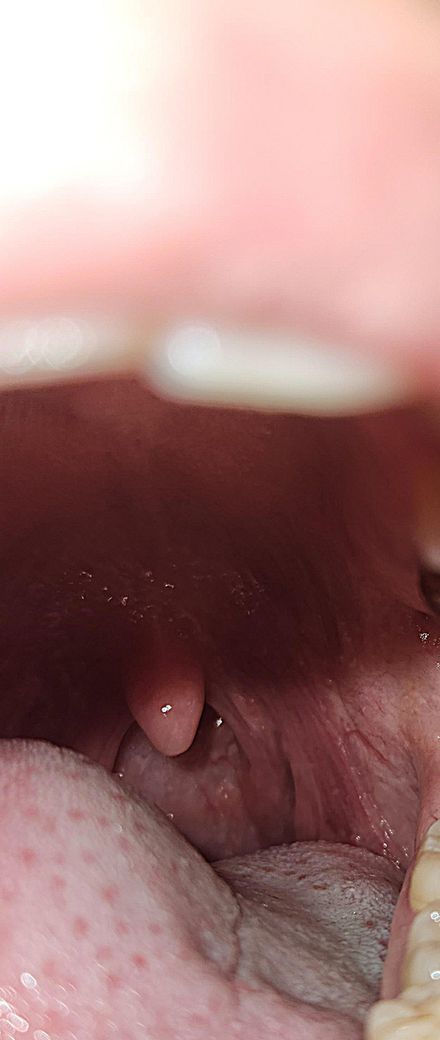

목이빨갛고부었다고했는데 수족구병변보이시나요?

목이빨갛게부어있다하셨어요.

오전에는 수포안보인다고하셨어요.

이정도 붓기와빨간정도면 열이날수도있을정도인가요?

• 2번 째 사진

사진을 보면 목이 많이 붉고 부어있는 것이 보입니다. 이 정도의 염증은 열을 동반할 수 있으며, 이는 신체가 감염과 싸우기 위해 반응하는 정상적인 과정입니다. 아이들의 수족구병이 있다면, 어른도 전염될 가능성이 있으므로 주의가 필요합니다. 수족구병의 경우 초기에는 인후염, 발열, 피로 등의 증상이 나타날 수 있으며, 이후 손, 발, 입안에 작은 물집이 생기기도 합니다. 오전에 의사께서 수포가 보이지 않는다고 하셨지만, 수족구병의 초기 단계일 수도 있습니다.